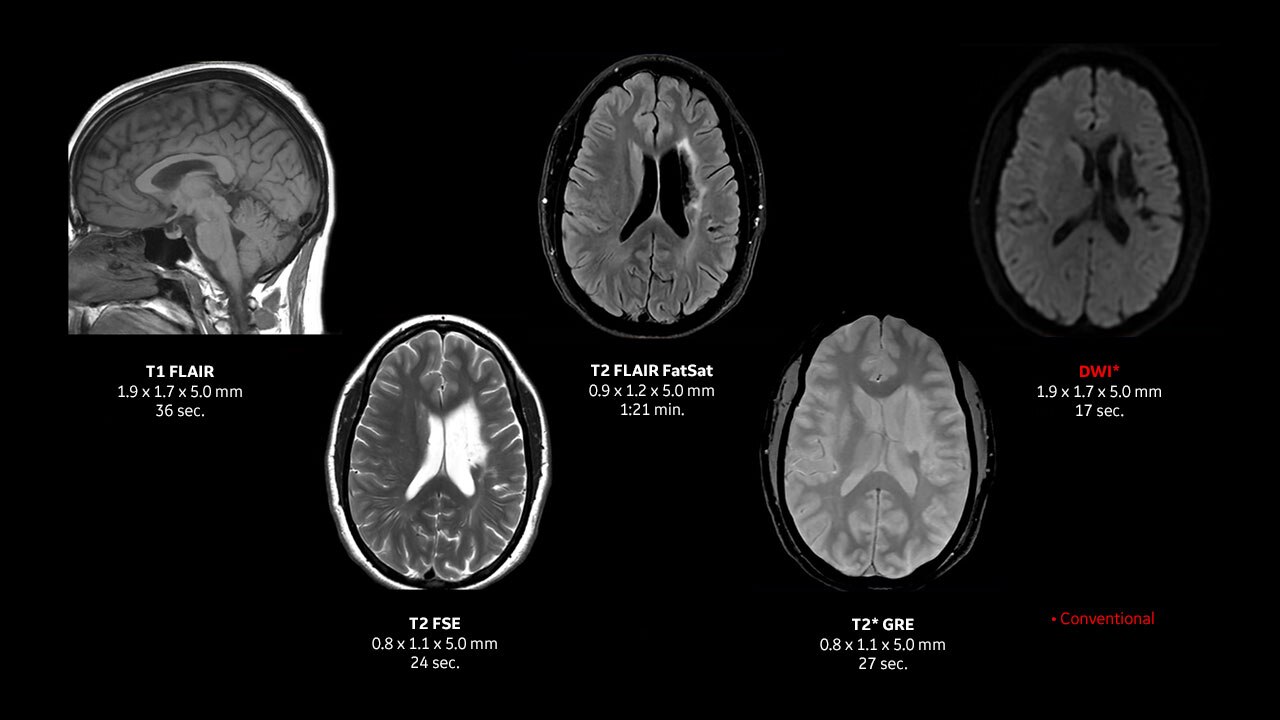

Achieve pin-sharp image quality with pioneering AIR™ Recon DL AI technology

With access to the latest advanced AI technology, you can scan all anatomies and achieve pin-sharp images. Our pioneering Deep Learning-based reconstruction algorithm AIR™ Recon DL accelerates scan time and puts patients at ease.